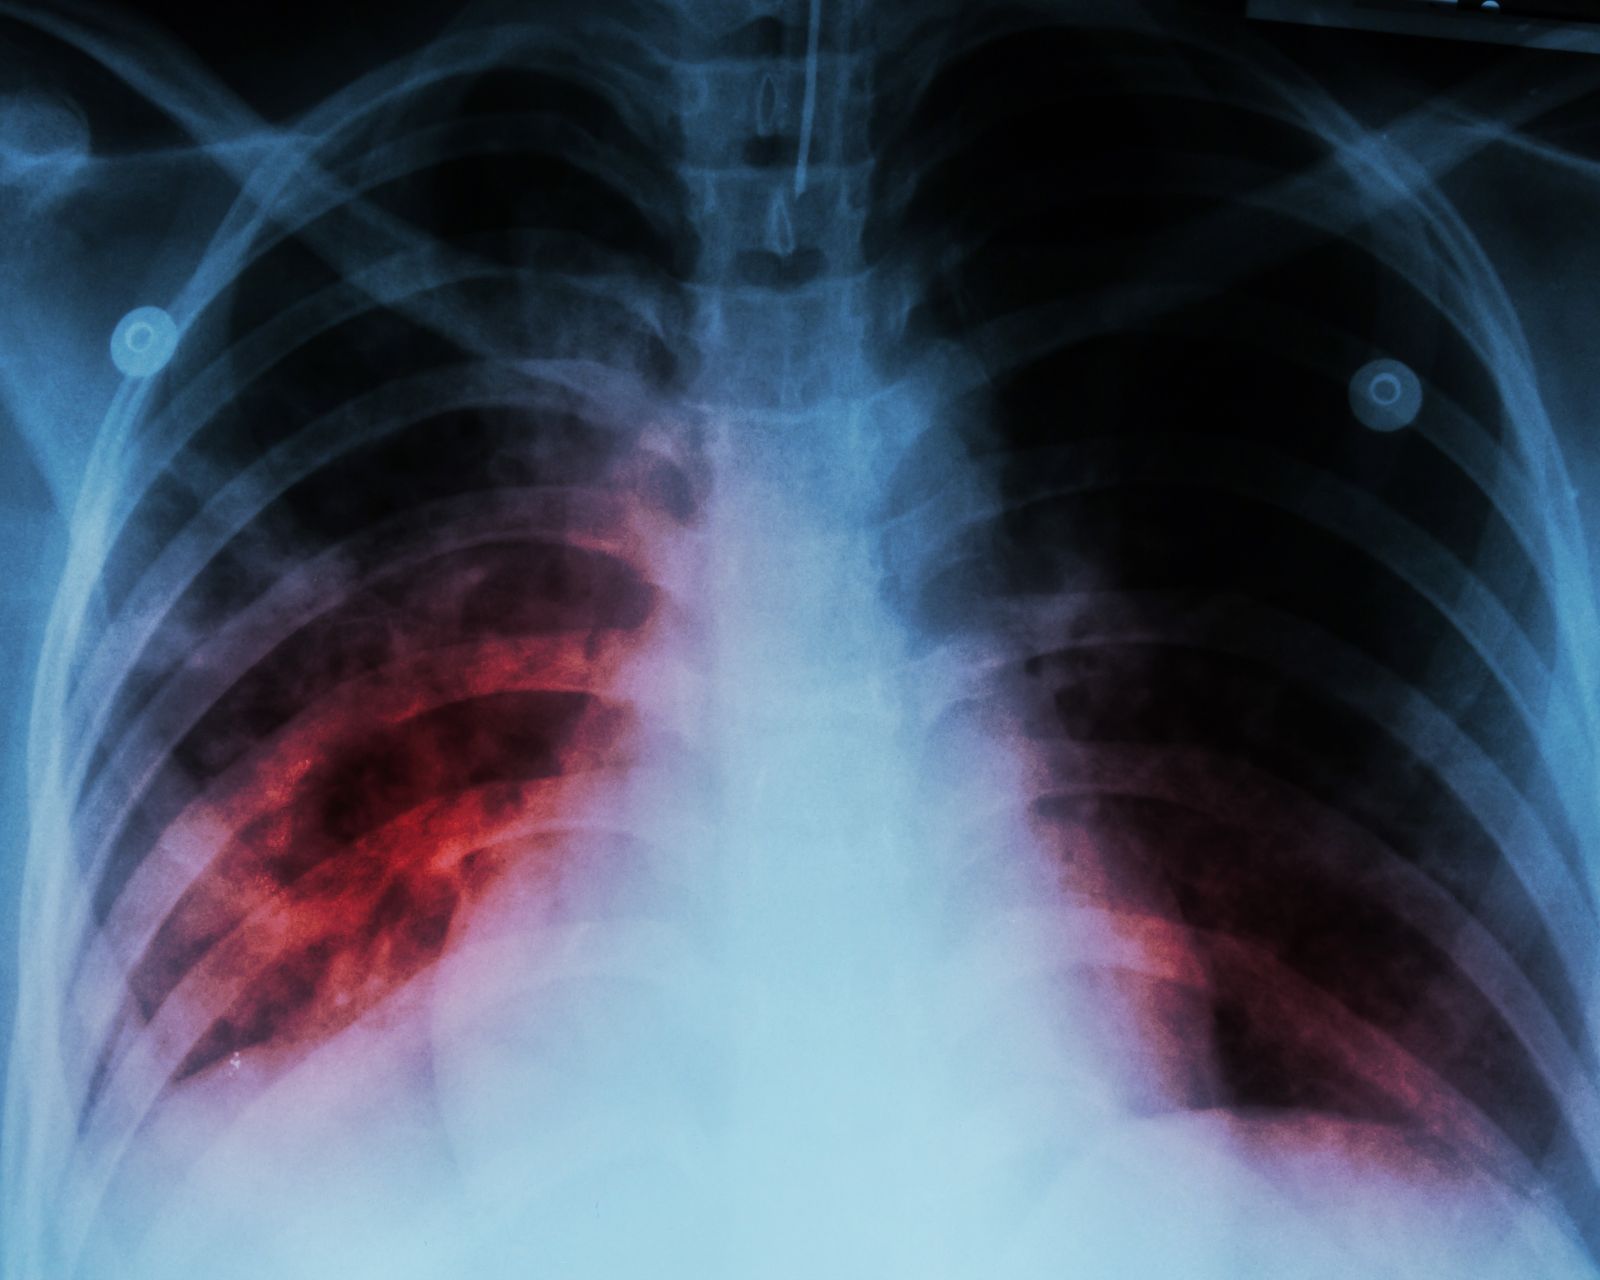

NIH grant boosts international TB research consortium

The Vanderbilt TB Center is returning to the leadership team of the RePORT International Coordinating Center, for its 3rd iteration.